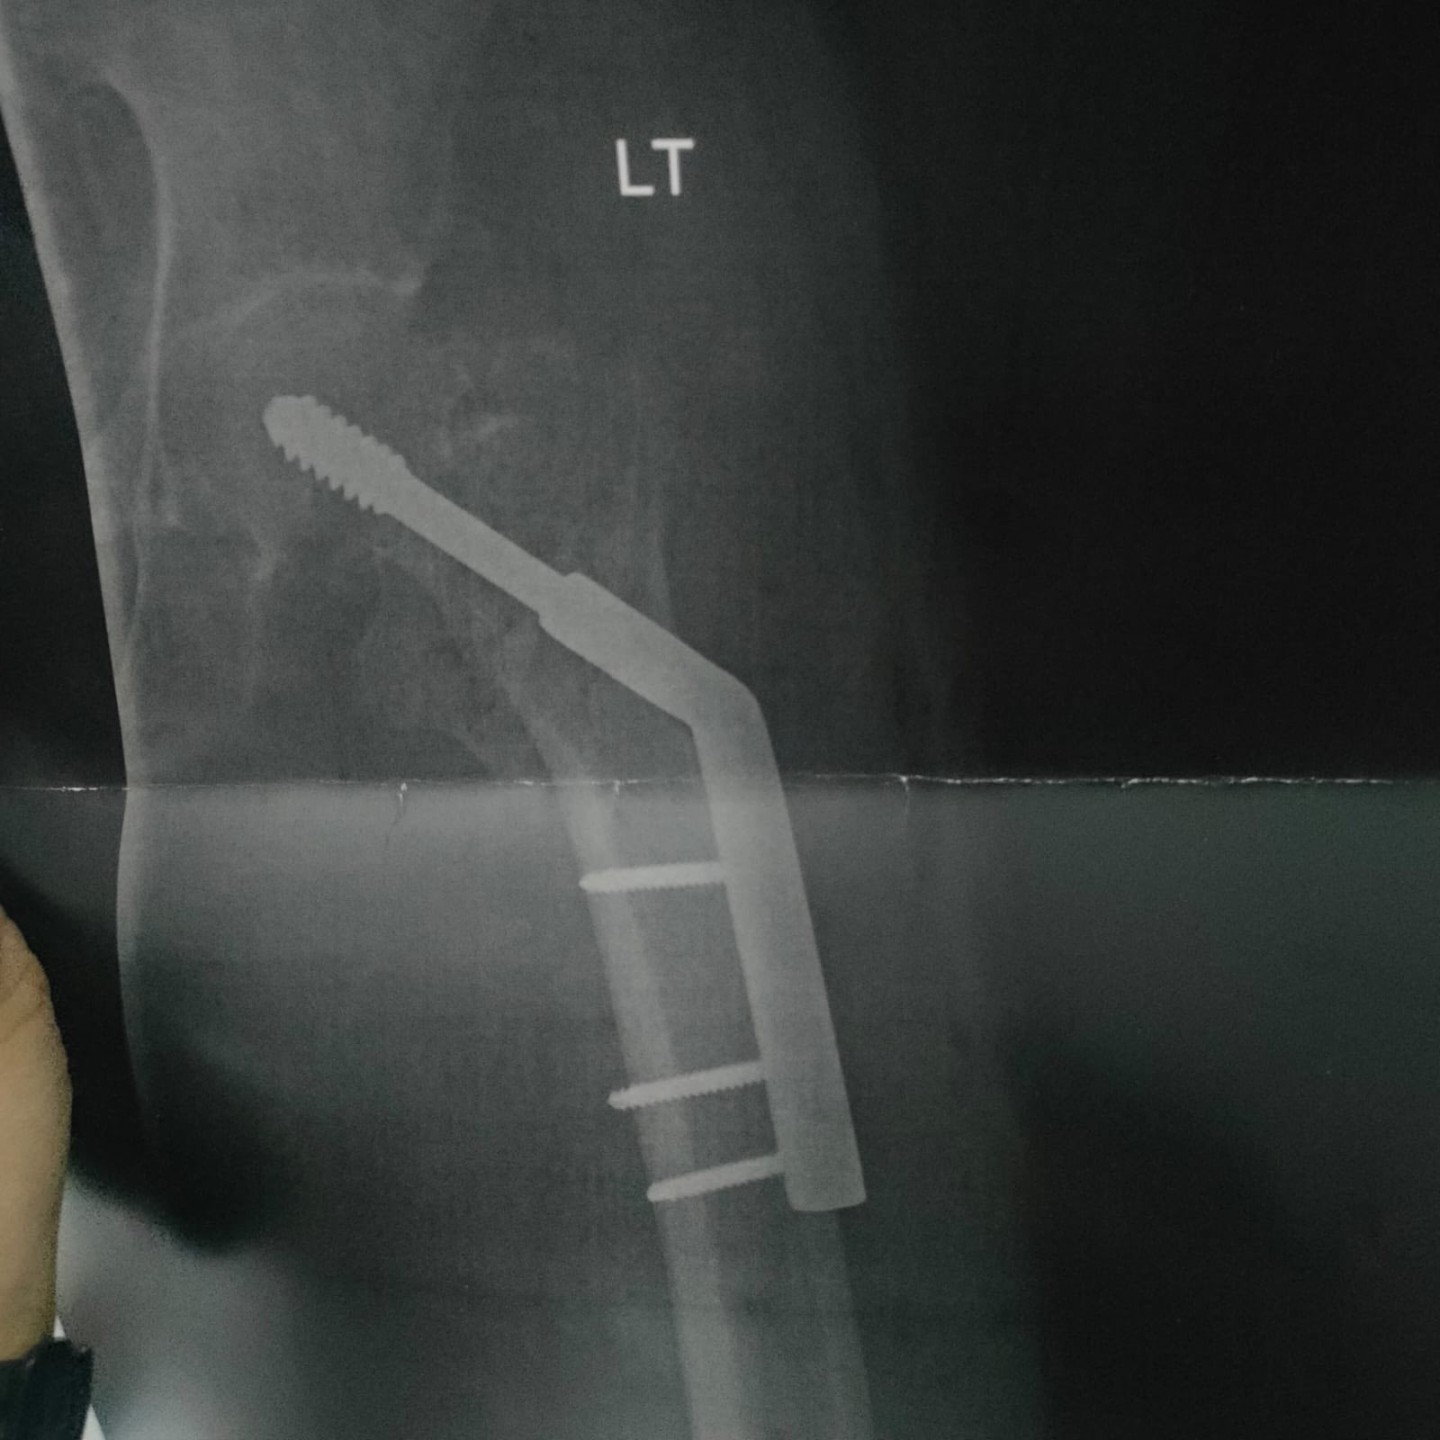

كما نجح الفريق الطبي ، في إجراء عملية مماثلة لمريض يعاني من كسر معقد بمفصل الفخذ حيث تم تصليح الكسر وتركيب شريحة ومسامير وتكللت العملية بالنجاح وغادر المريض المستشفى بحالة صحية جيدة

وضم الفريق الطبي الدكتور محمد سلمي، أخصائي جراحة العظام ، والدكتور رؤوف، نائب العظام ، والدكتور مينا لوقا ، طبيب التخدير، بمشاركة فريق تمريض العمليات